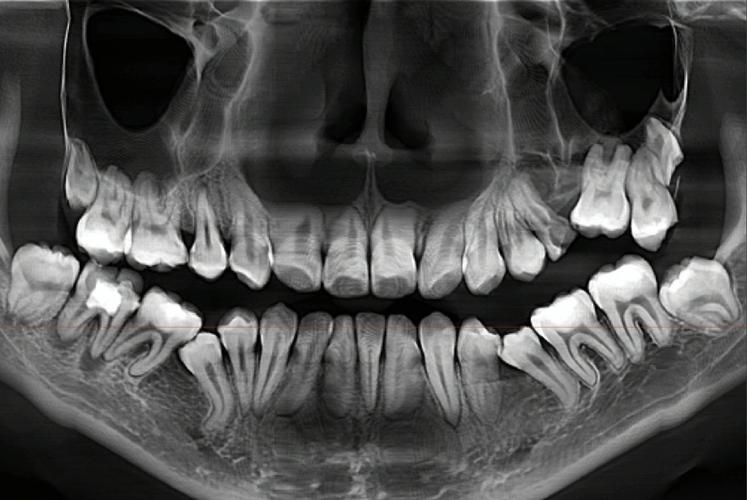

通过全景片(曲面断层片),可清晰观察全口牙齿的数量、形态及位置,包括是否存在“多生牙”(额外牙齿)、“缺失牙”(先天性或后天性缺失)、“埋伏牙”(未萌出的牙齿,如阻生智齿)等异常,若存在埋伏牙,需判断其位置、方向是否会影响矫正中牙齿的正常移动,或是否需要提前手术拔除;若存在多生牙,可能占据正常牙齿的生长空间,导致牙列拥挤,需在矫正前处理,还能观察牙根形态是否正常(如弯曲、短根),牙根周围是否有吸收或病变,这些因素直接影响牙齿移动的稳定性和安全性。

牙齿能否在牙槽骨中稳定移动,取决于牙槽骨的厚度、高度及密度,通过全景片和CBCT(锥形束CT),可测量牙槽骨的骨量是否充足,若牙槽骨过薄或存在吸收(如牙周病患者),牙齿移动过程中可能发生骨裂或松动,需先进行牙周治疗,调整移动力度和速度;若牙槽骨条件不佳,甚至可能需要植骨来为牙齿移动创造“安全土壤”。

牙齿的排列需与上下颌骨的协调关系匹配,否则即使牙齿排齐,也可能存在“深覆合”(上牙盖下牙过多)、“深覆盖”(龅牙)、“反合”(地包天)等咬合问题,影响面部美观和咀嚼功能,头颅侧位片是评估颌骨关系的“金标准”,可测量上下颌骨的长度、角度,以及牙齿与颌骨的相对位置(如ANB角、SN角等),判断是否存在骨性畸形(如下颌后缩、上颌前突),若存在严重的骨性问题,单纯矫正牙齿无法达到理想效果,需配合正颌手术,而手术方案的设计完全依赖头颅侧位片的精确数据。

颞下颌关节(TMJ)是连接下颌骨与颅骨的关节,负责张口、闭口等动作,若关节存在结构异常(如关节盘移位、骨赘),可能引发疼痛、弹响甚至张口受限,通过关节片或CBCT可观察关节形态,判断是否需要在矫正中调整咬合关系,避免加重关节负担,全景片还能发现颌骨内的囊肿、肿瘤等病变,防止在矫正过程中刺激病变进展。